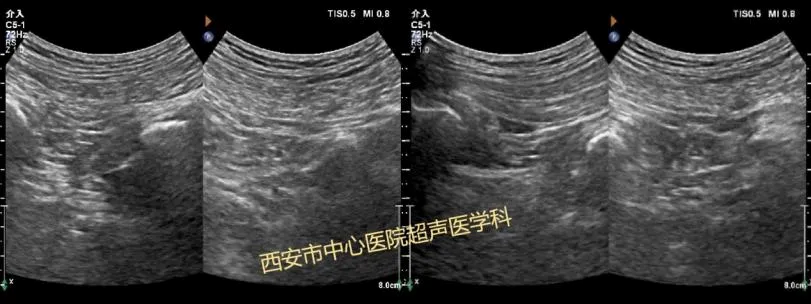

在医院里,王阿姨首先做了肌骨超声检查,确定右下肢疼痛是由于右侧梨状肌水肿,卡压住坐骨神经,确诊后,该院骨二科任波主治医师立刻联系超声医学科,经验丰富的超声医学科赵晶晶医师采用超声引导技术,精准定位右侧梨状肌、臀大肌及臀深肌间隙,进行注射治疗,同时对受压肿胀的坐骨神经实施水分离治疗术。

微创手术过程中,赵晶晶医师运用超声图像清晰呈现身体内部结构,确保注射位置精准无误!当药物缓缓注入,就像为受损部位送去修复的“精灵”,而坐骨神经水分离术则巧妙地为神经解压,让神经传导恢复顺畅。

超声检查是梨状肌综合征的首选检查手段,超声引导下可视化介入治疗是一种微创靶向治疗,优势在于:在超声引导下,医生能够实时监测到穿刺针的行径路线以及注射药物时药物扩散的情况,确保治疗药物直达病灶,实现最小有效剂量药物注射到病变组织,在治疗的同时,对神经与肌腱进行水分离,具有可动态监测,准确性高,不影响正常工作、休息等优点,同时避免传统疼痛注射治疗可能带来的不必要损伤,如肌腱或韧带内注药导致物理性损伤等。